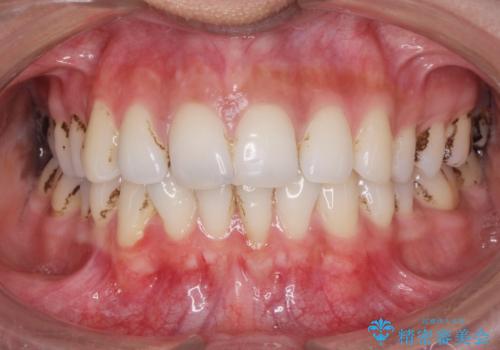

- 30代男性

- 歯ぎしりが気になるとの事で来院。

しっかりしたナイトガードが欲しいとの事だったので自費のナイトガードのご案内をしました。

ナイトガードは夜寝ている時、無意識に歯ぎしりをして歯がすり減ることを防ぐことがあります。また、歯が割れたり欠けたりするのも防いでくれます。